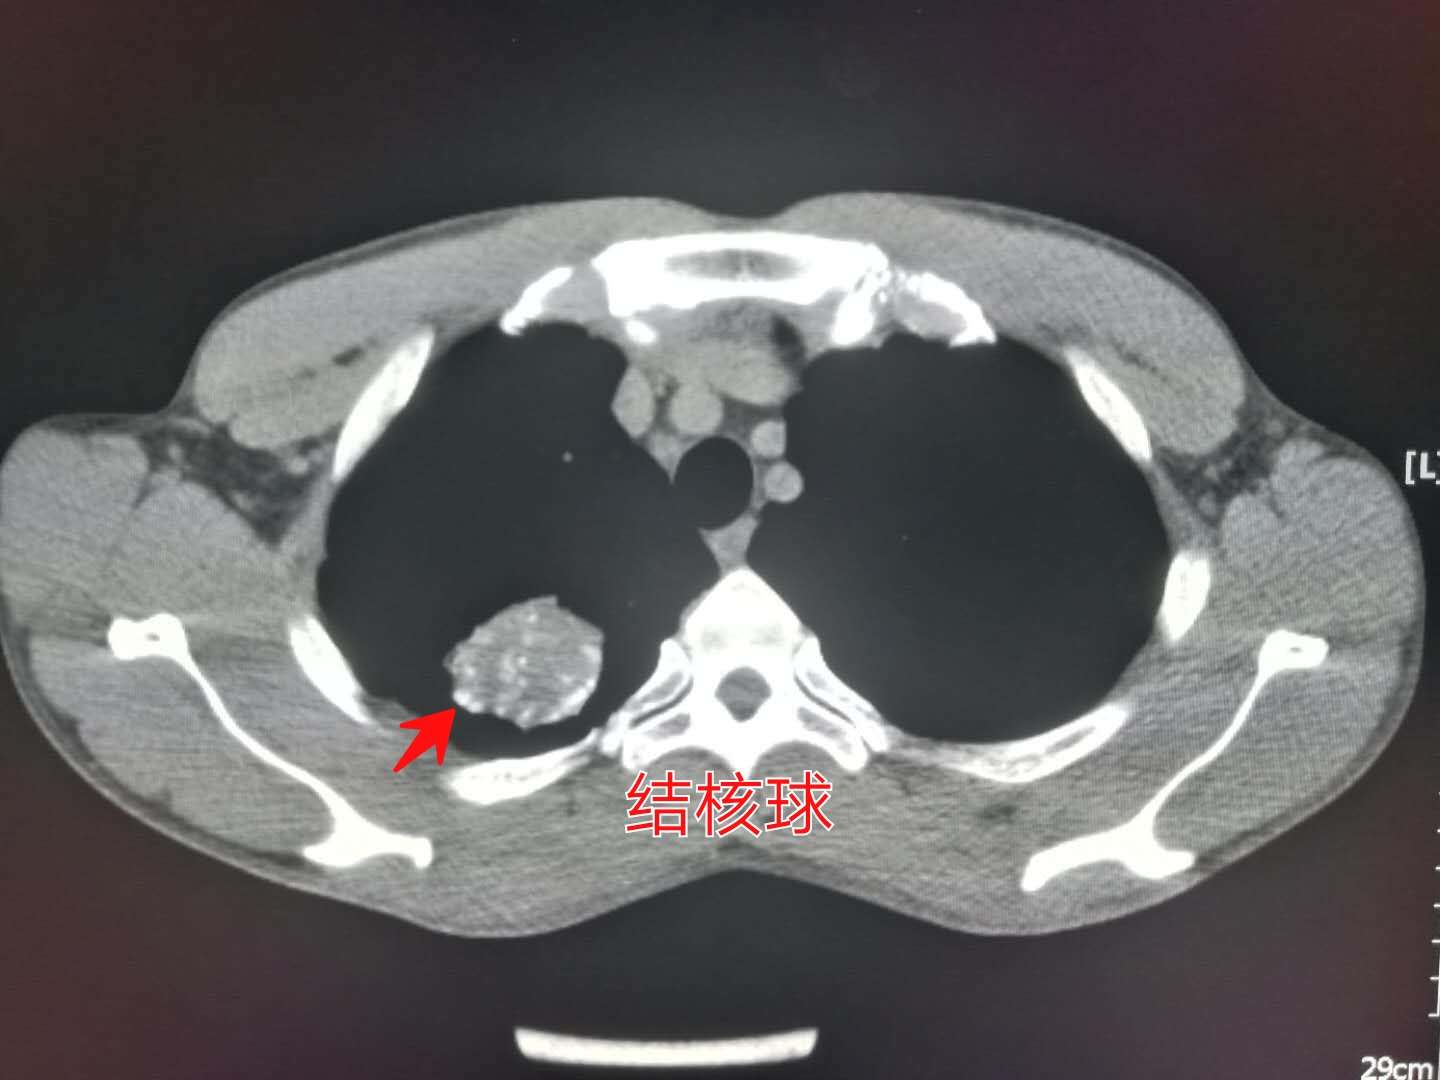

CT片上可以看到,右肺尖一个球形病灶,边界清晰,里面有多高斑点状的钙化,这个是典型的“结核球”。

观察他第一次的片子,在结核球的周围还有小斑片影和一些小结节(属于肺结核的卫星灶),本次已经基本吸收了,说明治疗有效。

我们从开篇第一张图中可以看出,小伙子的结核球属于孤立性病灶,伴有多发斑点状钙化,没有空洞,没有树芽征,也没有肺实变和磨玻璃密度影,气管壁没有增厚,说明不具备影像学的活动期表现。